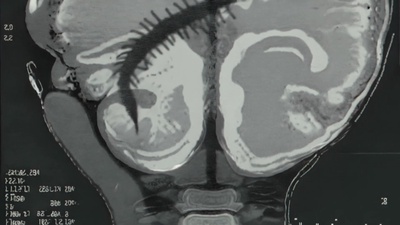

Recorded in a surge of impulse immediately after discharge from cervical spine surgery. Sequenced noise evoking compressed neural signals. A document of pressure, fixation, and release. The inaugural No-Input Mixing Works, Vol. 1.